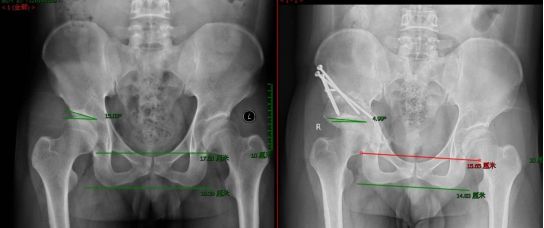

髋关节发育不良(developmental dysplasia of the hip, DDH)是指髋关节发育过程中出现的各种畸形,包括股骨头和髋臼的发育不良、髋关节半脱位以及髋关节脱位三种情况。正常的髋关节发育有赖于股骨头与髋臼之间的稳定性。成人髋关节发育不良多见于女性,有些患者毫无症状,仅仅在拍X线片示偶尔发现。大多数患者在20-40岁之间出现症状,早期症状表现为髋关节活动时的隐痛和酸胀不适感,长时间的行走后会加重疼痛症状,部分患者休息后不见缓解。髋臼周围截骨术能够有效地改善髋臼的覆盖、增盖加负重的关节面,使髋关节的旋转中心内移、减小髋关节负重面软骨的应力,从而达到预防和推迟骨关节炎发生目的。(如下图:该患者采取PAO手术,术前髋臼对股骨头包容差,头臼力学分布不均,术后明显增加了包容,生物力学分布更加合理)